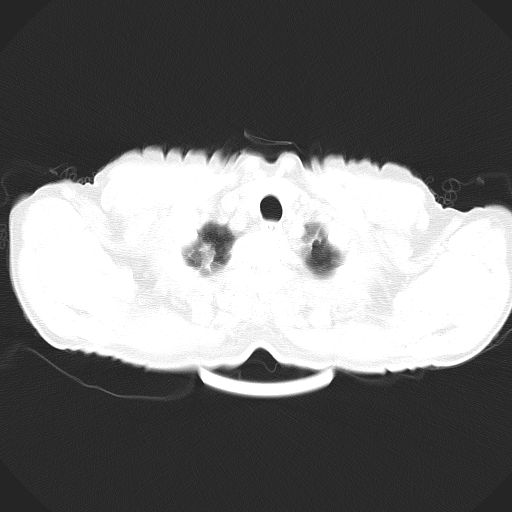

以下是引用心路寻觅在2010-3-1 10:23:00的发言:[br]1、考虑左肺上叶周围型肺癌[br]2、右上肺陈旧性病灶。[br][br][本贴已被 心路寻觅 于 2010-3-1 10:40:18 修改过]

以下是引用shuiyuan在2010-3-1 10:45:00的发言:[br]考虑左肺上叶中心型肺癌伴阻塞型炎症,邻近胸膜受侵。